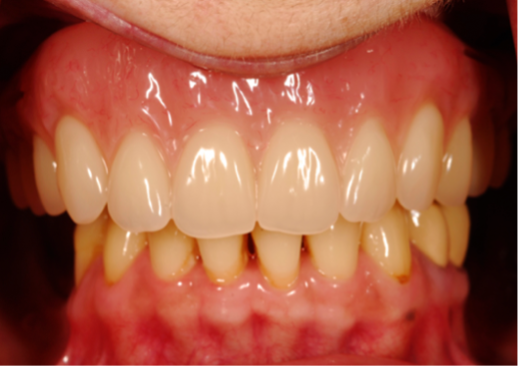

(13.) Prosthetic design allowing access to FMG interface.

Figure 13

(14.) Healthy Gingival Tissue.

Figure 14

(15.) FMG access and convex intaglio profile.

Figure 15

(16.) FMG access and convex intaglio profile.

Figure 16

Many factors should be considered when designing implant-supported restorations to reduce the risk of peri-implantitis affecting physical removal of bacterial plaque at the FMG. Included are oral hygiene devices, accessibility, prosthetic shapes, and patient ability to comply with oral hygiene procedures. The design should be conveniently hygienic so patients can easily comply with the recommended oral hygiene procedures. Physical removal of bacterial plaque on the intaglio surface at and above the FMG reduces the risk of peri-implantitis in the sub-gingival transmucosal tissue around dental implants. The original fixed prosthetic design presented by Branemark, a "High water design", provided access to all surfaces for oral hygiene management without a patient complaint of food accumulation (Figure 9 and Figure 10). Notably, relief above the gingiva was not patient complaint with this design. Lack of embrasure access to the FMG and intaglio surfaces for oral hygiene management can lead to peri-implantitis (Figure 11 and Figure 12). Stein recommended a convex modified ridgelap pontic design with lingual and palatal access to facilitate plaque removal from the intaglio surface under pontics in fixed prosthetics with dental floss.20 These shapes should be standard for fixed implant-supported restorations whether individual or multi-unit restorations made of ceramo-metal or milled zirconia (Figure 13 through Figure 16).